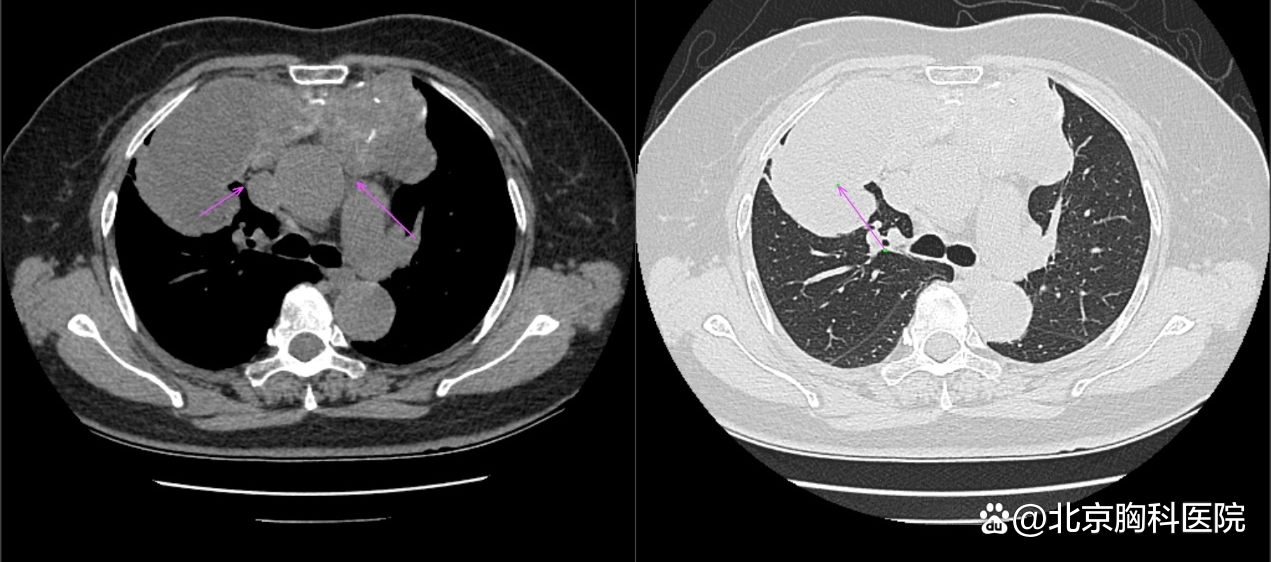

图:侯阿姨的CT片,肿物主要位于右侧纵隔,波及左侧,压迫右肺上叶(右图长箭头),但与上腔静脉(短箭头)和主动脉(长箭头)界限清晰

对于侯阿姨的病情,刘志东主任根据CT检查做出了精确的判断:“虽然这个患者肿物比之前老康的更大,但与周围组织尤其是主动脉、上腔静脉、心包等界限清楚,并未发生侵袭,右肺上叶主要为压迫性肺不张,整体手术难度低于老康。”在刘志东主任的带领下,纵隔外科团队又向纵隔肿物发起了挑战。经术中探查,病变位于前上纵隔,大小约12cm×14cm×10cm,质地较硬,侵及右肺上叶,且右肺上叶部分肺出现肺不张、肺实变。在此情况下,刘志东主任团队仅用30分钟,就完成了纵隔肿瘤的切除,纵隔外科团队再次创造了奇迹。